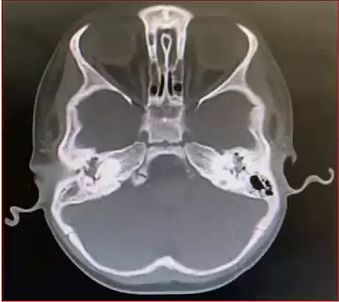

Sim. Se possível pedir ambos:

• TC é indicada para avaliação da permeabilidade coclear, pesquisa de malformações ou características sindrômicas e estudo da anatomia cirúrgica

Estabelecer valor preditivo de sucesso ou de falha para o procedimento e avaliar prioridades. Por exemplo, pacientes com síndrome de Usher devido a chance de cegueira tem prioridade para realização do IC. Meningite pode causar ossificação rápida. Então o processo de IC também deve ser realizado precocemente. Após ossificar a cóclea se torna impossível realizar o implante (imagem).